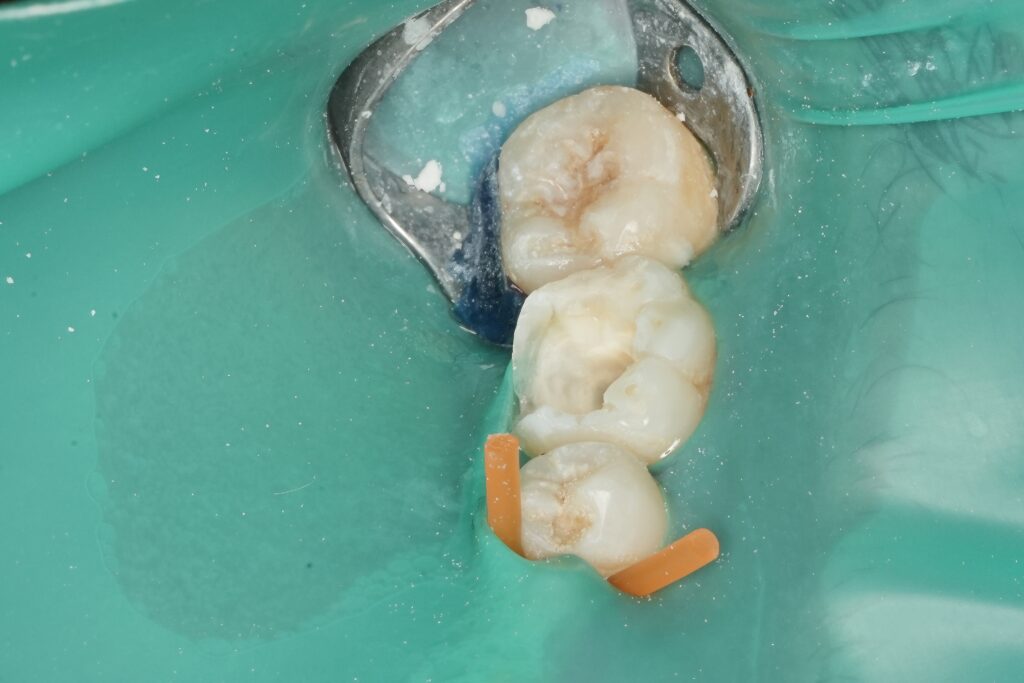

After anesthesia, the tooth was isolated using a rubber dam to ensure asepsis throughout both endodontic and restorative phases. Access cavity preparation was carried out conservatively, prioritizing preservation of pericervical dentin.

The tooth was re-isolated under rubber dam. Enamel margins were refined and selectively etched to maximize enamel bonding while protecting dentin. A multi-step adhesive protocol was used to ensure optimal hybridization and marginal integrity.

The onlay was built incrementally using a stress-reduced layering technique. Cusps were reconstructed anatomically, respecting occlusal morphology and functional pathways. Occlusion was carefully adjusted to avoid high-stress contacts, particularly in lateral excursions.